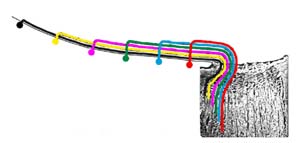

Technika vyšetření vrstvy nervových vláken

Pomůcky: štěrbinová lampa, 90 D čočka a fixační světélko na protější straně místnosti.

Nastavení lampy: zelené světlo paralelně s osou našeho pohledu, paprsek co nejvíce vertikálně protažený, aby pokryl oblast horních i dolním temporálních nervových svazečků. Zaostříme na terč tak, abychom ho viděli prostorově.

Pohybem štěrbinové lampy pak světelný proužek posuneme mezi terč a foveolou. Pohledem srovnáváme žíhání sítnice směrem dovnitř od velkých cévních kmenů, srovnáváme rozdíl mezi horními a dolními svazky vláken. U zdravého oka bývá žíhání a zastření cévních kmenů směřujících do makuly výraznější v dolní polovině sítnice než v horní.